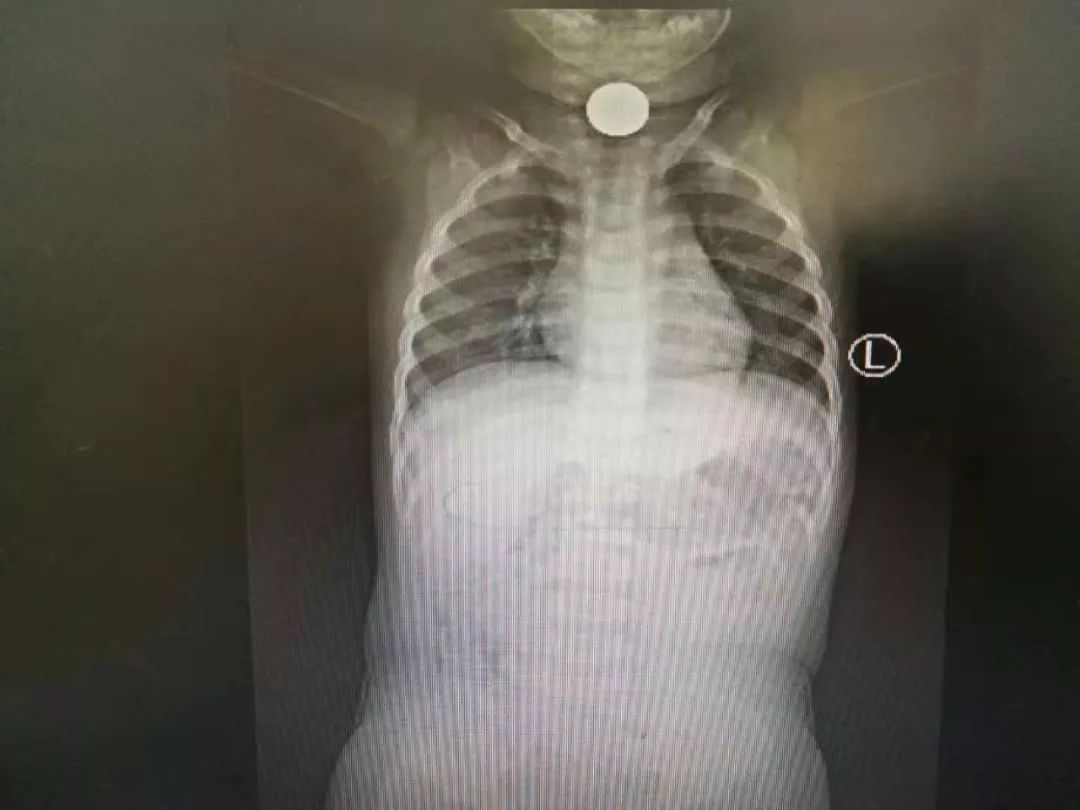

诊室医生拿着纤维鼻咽内窥镜检查后发现,在孩子的右侧鼻腔里有一个黄色的异物,一碰比较硬,表面还附着着大量的脓涕。医生拿药物收缩鼻腔黏膜后,在纤维鼻咽内窥镜的救治下,竟然取出了一只蜗牛。

“一开始,我们以为是一个玉米粒,结果当我们把异物钩出来后发现,竟然是个直径4~5毫米的蜗牛。”该诊室主任李为告诉记者。